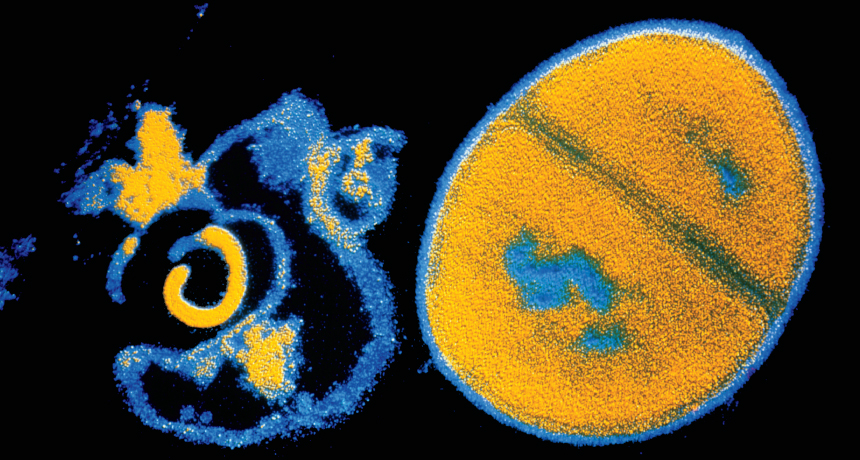

BATTLING BACK  Antibiotics such as penicillin attack a bacterium’s cell wall, bursting it (left, shown next to an intact Staphylococcus aureus cell in false color). Some studies suggest that antibiotics also trigger other kinds of damage that could be harnessed in the battle against antibiotic resistance.

CNRI/Science Source

Penicillin attacks with a calculated strike, splitting open cell walls.